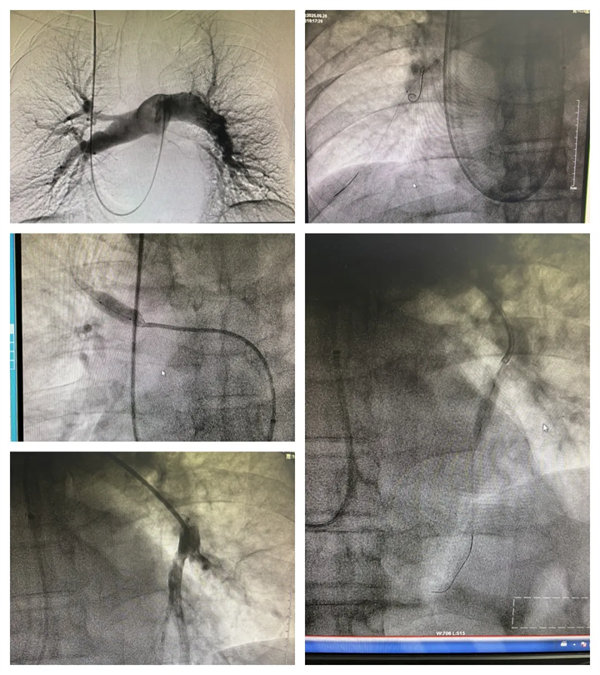

近日,宝鸡市人民医院心血管内一科成功为一名慢性血栓栓塞性肺动脉高压患者实施右心导管测压+肺动脉造影+肺动脉球囊扩张成形术,该手术的成功开展,填补了我院心血管内科此项技术的空白,进一步完善了心血管内一科在肺动脉高压领域的长时程治疗管理体系,为慢性血栓栓塞性肺动脉高压患者带来了新的治疗选择。

心血管内一科医护团队一致认为患者需行右心导管测压、肺动脉造影、肺动脉球囊扩张术。与患者及家属详细沟通后,同意手术治疗。术前准备就绪后,在西安交通大学第一附属医院张松林教授指导下,心血管内一科主任翟向伟、副主任医师陈万林及介入导管室团队密切配合,顺利完成手术。因患者之前植入的下腔静脉滤器未取,手术团队穿刺右侧颈内静脉经导管测平均肺动脉压力50mmHg(重度),进一步行肺动脉造影提示患者双侧肺动脉多发严重狭窄,部分肺动脉闭塞。介入团队随后依次对左右肺动脉狭窄病变进行球囊扩张成形术(共扩张肺动脉5支),术后患者胸闷气短症状明显减轻。经过医护团队的精细治疗及护理,患者顺利出院。择期将再次行肺动脉球囊扩张术。